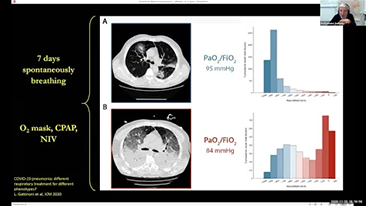

A partir de un profundo conocimiento de las necesidades clĂnicas tanto de los pacientes como de los profesionales, los respiradores Mindray respaldan los requisitos del tratamiento secuencial de oxigenoterapia, ventilaciĂłn no invasiva y ventilaciĂłn invasiva con un rendimiento estable, funciones versĂĄtiles y facilidad de uso. Los modos de ventilaciĂłn y las herramientas de apoyo de la toma de decisiones se dise?aron teniendo en cuenta las necesidades clĂnicas y las directrices profesionales con la finalidad de ayudar al personal mĂ©dico a tomar decisiones cĂnicas con calma en relaciĂłn con todos los grupos de pacientes y todos los niveles de agudeza.

La elecciĂłn de la configuraciĂłn correcta del respirador para el tratamiento de pacientes con enfermedades de las vĂas respiratorias es un asunto muy importante. Dado que un mĂ©dico es responsable de la tarea de especificar los parĂĄmetros del equipo de ventilaciĂłn en su totalidad, el conocimiento y la experiencia del mĂ©dico en la selecciĂłn de estos ajustes tiene un efecto directo en la precisiĂłn de sus decisiones. El paradigma de la atenciĂłn de apoyo de los pacientes ha cambiado significativamente durante los Ășltimos 20?a?os. Hoy en dĂa, se han desarrollado varios modos de ventilaciĂłn y herramientas de apoyo de la toma de decisiones en torno a las necesidades clĂnicas para ayudar a los profesionales a mejorar la eficiencia y eliminar errores en estas decisiones.